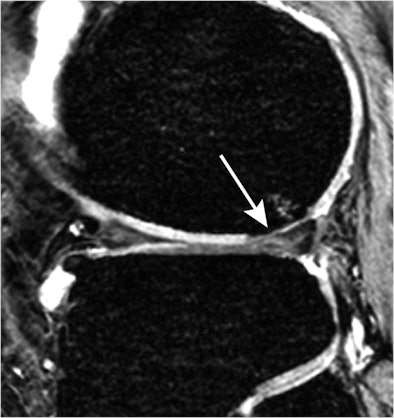

| Sagittal 3D gradient-echo MR image shows cartilaginous defect (arrow) and bone marrow lesion in lateral femoral condyle in a 54-year-old woman with ACL rupture and meniscal tears 10 years ago. The sequence was used to score the cartilage lesions. Fat-suppressed fast spin-echo sequence was used to score the bone marrow lesion. The ACL rupture was not reconstructed, and the medial meniscal tear was treated with partial meniscectomy. Image courtesy of Radiology. |

In the analysis of MR images, the researchers found that patients with anterior cruciate ligament (ACL) ruptures had an increased risk of developing joint space narrowing, cartilaginous defects, osteophytes, bone marrow lesions, and subchondral cysts medially or laterally.

The different patterns of developing osteoarthritis are determined according to the initial ACL and meniscal injuries, they also noted. "The hallmark finding of osteoarthritis development after medial meniscal tears is diffuse medial cartilage loss, and after lateral meniscal tears, it is focal lateral cartilage loss. After ACL rupture, osteoarthritis characteristics are seen medially and laterally," they wrote.